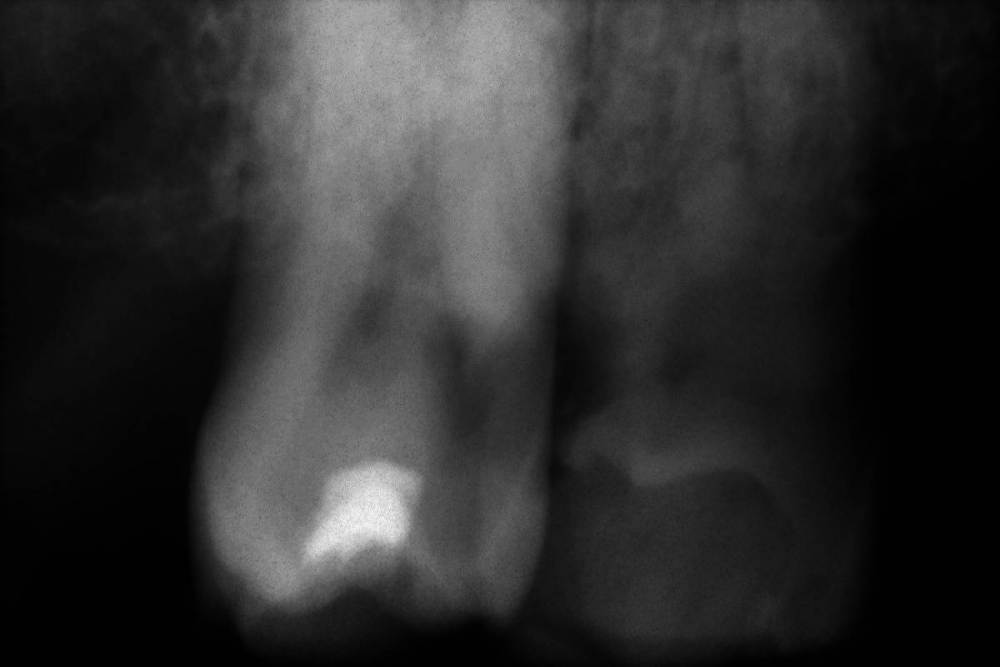

GENRY Опубликовано 6 сентября, 2021 Поделиться Опубликовано 6 сентября, 2021 Здравствуйте! Как лучше восстановить ( пусть частично) 28 зуб? Удаление не желательно т.к. с имплантацией связываться не хочу (синус лифтинг.. возраст 75 лет...) ,а опор для ортопедических конструкций нет. Кроме того боюсь, что в процессе удаления будет разрушена пломба 27 _го. Оптимизма добавляет история 27 го На орто 2012г показан 27 до его восстановления и до вмешательства в 28 зуб с добавлением в него пломбы в 2012г . Канал 28_го (небный ?) был уже запломбирован кем то раньше, скорее всего резорцин-формалиновой пастой) Доктор в 27 - м обнаружил на снимках 3 канала, наполовину прошел небный и полностью прошел дистально- щечный канал с наполнением их горячей гуттаперчей . Поскольку устье 3_го канала обнаружено не было, восстановил 27 зуб 2_мя стекловолоконными штифтами с использованием Build-It . Дистальную стенку сделал, кажется на основе пасты СПЕКТРУМ . К дальнейшей судьбе 27_го доктор отнесся скептически ( не более 2_х лет!), но похоже сработал надежно, пошел уже 10_й год, а 27 все стоит. Но 10 мес. назад выпала пломба 28 _го и он принял вид показанный на снимке. Не беспокоит. Хотелось бы повторить историю с 27_м, т.е. восстановить 28 по типу 27_го .... думаю мне хватит 5_7 лет... Регулировать нагрузки на этой стороне челюсти я научился. Сделал КТ сегмента 27_28 (В Пикассо, Vatech, просмотрщик EZ3D2009 plus ) но не смог найти ( сейчас живу в Феодосии ) терапевта работающего с этой программой. Кто то вообще не использует никакие КТ (но при этом берется за восстановление штифтом без перелечивания каналов) , кто то готов к перелечиванию, но полагается только на свои мануальные навыки, игнорируя КТ или формально глянув на пару проекций. На последней консультации добился 4-х снимков из КТ, но в общем то случайных и скорее всего не показательных.. Выкладываю скриншоты... Понял, что надо выходить за пределы городка и расширять собственное (к сожалению) понимание возможных вариантов лечения и их последствий. Вопросы по 28: 1. Если хотя бы один канал запломбирован (видимый на снимке) то это автоматически означает вскрытие камеры , а значит вскрытие и убитость содержимого (нервов, сосудов) всех остальных каналов , поскольку их устья на дне камеры? (Да, Нет, Другое) 2. Если Да, то нормально ли было пломбировать 28, не найдя и не залечив (с пломбировкой) другие каналы одновременно с небным (я имею ввиду сейчас самую раннюю пломбировку, до представленного орто) 3. Поскольку пломбировки всех каналов (сколько их ?) точно не было, то за эти 10-15 (?) лет (уже сейчас зуб стоит открытым почти год (ковид, консультации..)) должен развится пульпит, периодонтит... ? Или не обязательно? Ничего не болело, никаких выделений не было 4. Есть ли признаки какой либо хроники, воспалений в тканях на снимках? 5. Если ткани зуба и около него в порядке, то может не обязательно перелечивать все каналы, чтобы не ослаблять зуб? А только те, в которые будут вставлены штифты? Вкладка, похоже исключается т.к. феррул не замкнут на стыке с 27 зубом. 6. Есть ли какие либо оценки минимального количества требуемых штифтов ? 7 . Поскольку за 4 консультации я так и не получил ответов и снимков срезов (по КТ )показывающих количество и топологию корней и каналов, то придется добывать эту информацию самому. Буду благодарен за ссылки на материалы показывающих как это делается т.е. в каких из 3 проекций, при каком положении осей и.т.п. Я нашел только хороший ролик Ервандяна А.Г., но мне недостаточно, не хватает знания топологии зубов. Спасибо за внимание. Ссылка на комментарий

GENRY Опубликовано 6 сентября, 2021 Автор Поделиться Опубликовано 6 сентября, 2021 Поясню свое стремление сохранить 28-ой, похоже здесь "возрастное" непонимание. Мне 75 т.е. согласно статистике для мужчин из РФ, в среднем осталось жить лет 6. Зубы еще год назад как то работали (пусть и с патологиями, нарушениями механики и.т.п.)..приспособился. Если бы такое состояние продолжилось еще 6 лет _ меня бы устроило.. Т.е вопрос для меня не в том, чтобы все в этом углу соответствовало стоматологическим канонам, а можно ли вернуться к состоянию : год назад? В 2012 был снят кусок 28 _го, примыкающий к 27 _му (наверное мешал реставрации 27_го) и заменен пломбой. Каналы не трогались. Вряд ли они были герметизированы этой пломбой от среды, кроме одного _запломбированного. Но зуб простоял 9 лет. 10 мес. назад эта пломба выпала. Возможно за эти годы в системе среда _каналы_кость ничего не изменилось и простое добавление пломбы (со штифтами или без) вернет зуб в прежнее состояние и я спокойно уйду с ним в мир иной. Меня это устроит. И не надо мне в этом случае ни удаления. ни имплантов, ни ортопедов. А может в системе среда _каналы_кость уже произошли изменения (инфицирование, хроника, воспаления и.т.п ) и такой вариант не прокатит? И это уже видно по снимкам? Тогда другое дело...здесь и возникают удаления. импланты, ортопеды. А может еще этих изменений нет, но они могут возникнуть при препарации...прохождении каналов (может они зацементировались сами?, а мы их вскроем)... и.т.п. Тогда как снизить риски такого развития событий? Для выяснения , какая ситуация имеет место, и нацелены мои вопросы.. Ссылка на комментарий